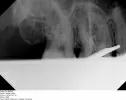

Во время отдыха у меня началось сильное воспаление над пятым и шестым зубами верхней челюсти. В шестом стоит старая пломба. Дантист поставил диагноз, который звучит как «16 симптоматический верхушечный периодонтит с щечным свищом».

Насколько это серьезно? Мне кажется, или в шестом зубе действительно есть перфорация к верхушке корня? Как это лечить, чтобы сохранить зуб? Врач отказался очищать каналы от старой пломбы под предлогом, что один из трех каналов слишком узкий и кривой, и послал меня к эндодонтисту. А его долго ждать надо. Нужно ли пить антибиотики? Посылаю рентген, чтобы Вы могли оценить ситуацию.

На этом снимке ничего не видно и поставить однозначный диагноз, вернее решить судьбу зуба невозможно. Шансов на полное выздоровление данного зуба очень мало, но попробовать пролечить стоит, если, конечно, нет перфорации. В гос. поликлинике это воспаление Вам никогда не вылечат, поэтому обратитесь к опытному специалисту.